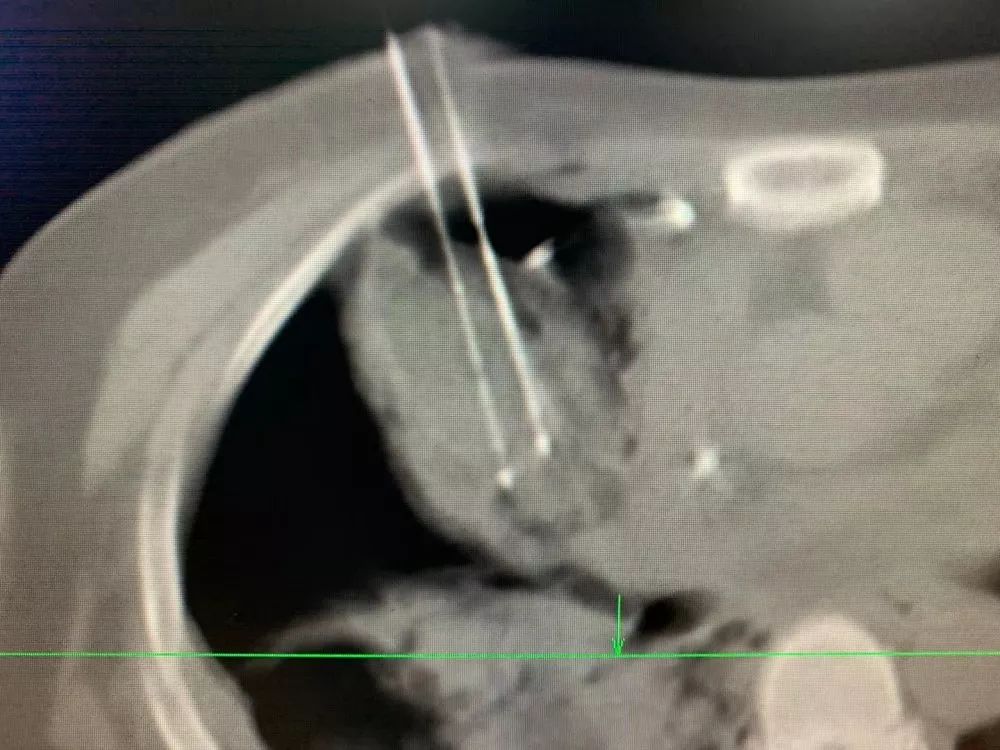

冷冻消融中

副院长牛立志教授为主刀医师,当手术开始,牛教授先用一根冷冻针像“钓鱼”一样把肿瘤“勾”住,然后慢慢从靠近心脏的危险地带中钓出这条“毒鱼”,把它放在安全的区域进行冷冻消融,尽可能避免对心脏造成损伤。因为心脏布满丰富的血管,肿瘤靠近心脏,一旦触碰到大静脉极易引起出血。这个看似简单的过程却十分考验一个医师的经验,既高度集中精神将肿瘤移出消融,也要时刻紧盯着心脏等重要器官是否正常运行。整个手术不允许有丝毫的偏差,耗时一个多小时才结束。